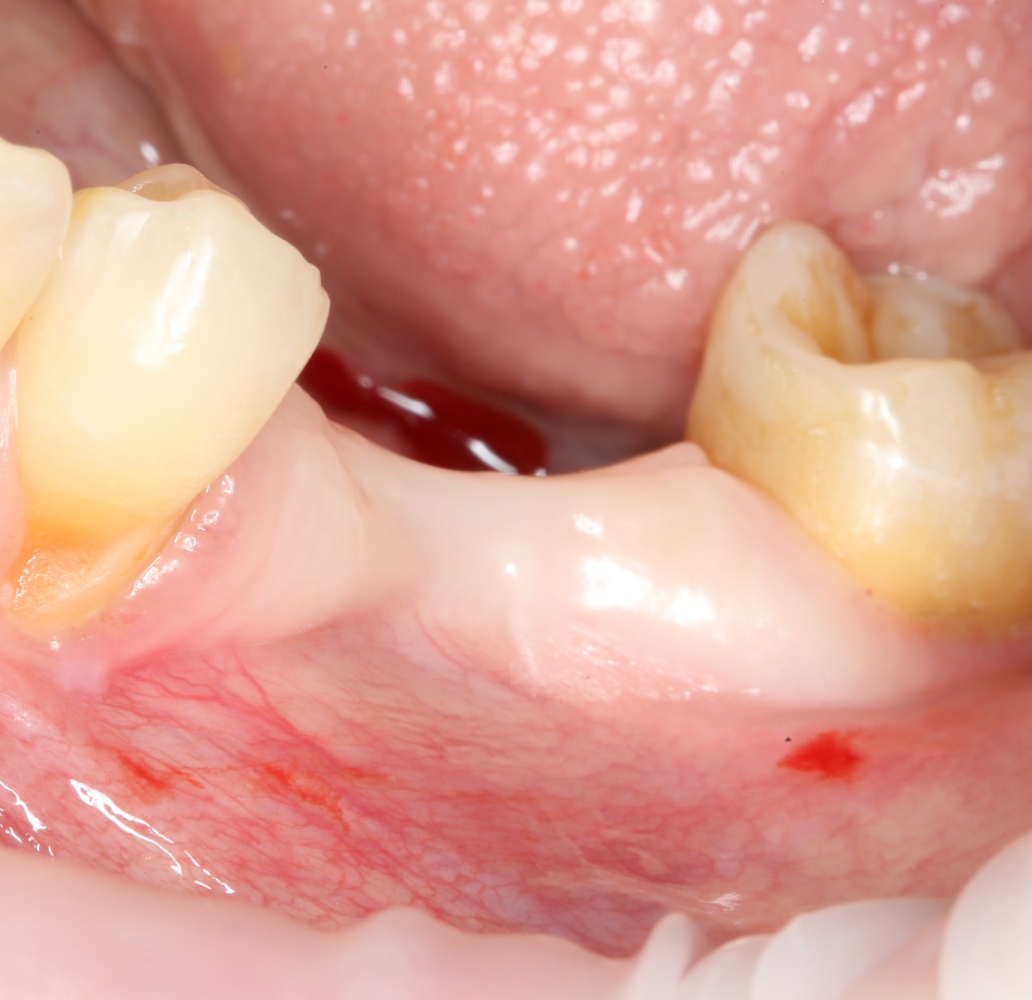

Но вот проблема — при длительном отсутствии зубов, травматичном удалении или из-за воспалительных процессов костная ткань альвеолярного отростка нижней челюсти атрофируется, меняет свою конфигурацию. Иногда довольно значительно:

A09A6305 (2) A09A6306 (2)

Можно ли в таких условиях поставить импланты? Скажу честно, можно. Но эти импланты будут короткими и тонкими, а находиться будут в таких положениях, в которых ортопеду будет очень сложно (иногда даже просто невозможно) их нормально протезировать.